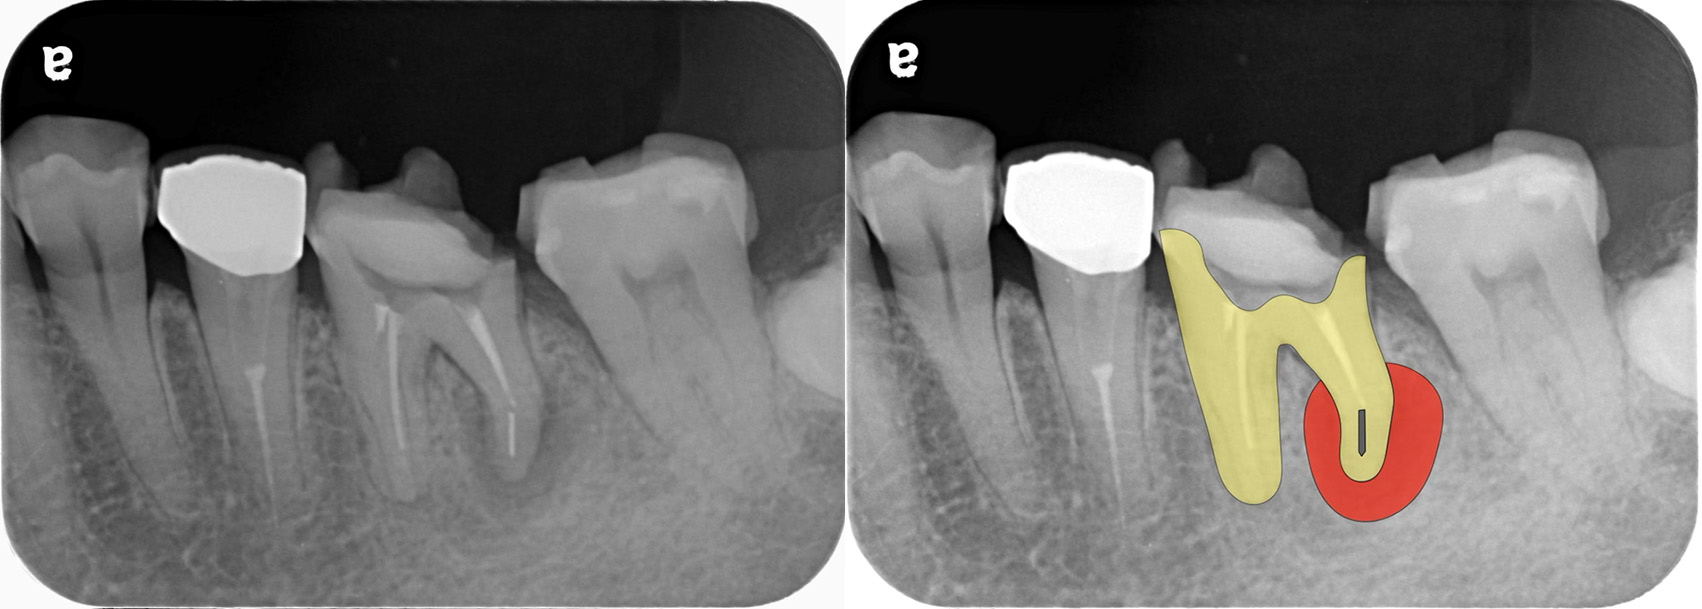

X線画像撮影(デンタルX線画像+歯科用CT画像)

虫歯の深さ・歯の残っている量・根尖部透過像(レントゲンに映る膿の影)の有無と大きさ・根管の数と形

根管治療を行う際は、基本的に入っている詰め物や被せ物は一旦全て取り除いてから行います。被せ物(特に金属の被せ物)の下はX線画像では映らない虫歯が残っている可能性があり、それが原因で歯の中に細菌が入ってきている可能性があるので、それらを取り除く必要があります。

レントゲンでは明らかな虫歯が確認できないですが

はずしてみると、中は虫歯(薬液で青く染まる)で汚染されていて、根管の中まで感染していました。そしてそのう蝕を全て取り除き、根管に器具が入れられる必要最小限の穴を開けていきます(髄腔開拡)。